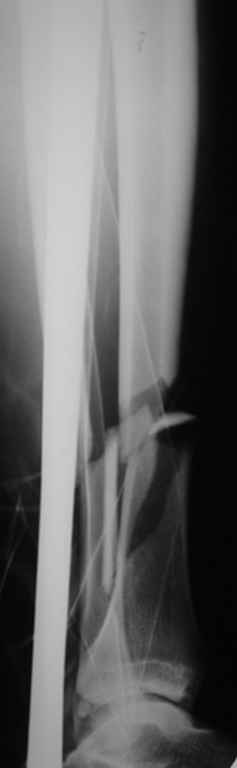

Вопрос с голенью сложен и наверняка в теч следующих суток д-двух Вы получите разные и противополножные предложения ( в том числе и Илизарова. и открыто гроздь\пластину, и закрыто).

Я бы закрыто на вытяжении ( чтоб меньше травмировать мягкие ткани - ассистент никогда не сможет удержать вправленную ногу совершенно неподвижно) штифтовал бы низкопрофильным штифтом. По окончанию штифтования, если мышечный футляр собрал отломки более-менее "в кучу" - не стал бы открывать. Если же после штифтования промежуточные отломки будут стоять совершенно неудовлетворительно - постарался бы через небольние разрезы подтолкнуть их на место. Мне кажется, что лучше через несколько недель или месяцев в случае несращения вернуться назад и добавить на место перелома аутотрансплантат из крыла подвздошной кости. чем сейчас добиваться хорошего сопоставления на крайне компрометированных высокоэнергетическим переломом мягких тканях

На голени что-то сделать с отломком вынуждает угроза перфорация кожи, перекрытие отломком входа в канал. Не всегда надо делать разрез, можно и шилом чрескожно фрагмент сдвинуть. Наверно, еще и повреждение сосудистого пучка, когда "виновник" прямо поперек перерезанной артерии и лежит - такое не каждый за всю свою профессиональную жизнь

встретит.

То есть в представленных ситуациях при штифтовании ни на бедре, ни на голени не нужно делать ни открытую, ни закрытую (с помощью шильев,

спиц, еще каких-то "джойстиков") репозицию. Все, что нужно - восстановить ось, длину и ротацию.

Перелом большеберцовой кости почти околосуставный, могут потребоваться дополнительные меры для восстановления оси (отклоняющие спицы или винты), и запирающих винтов в дистальный отломок желательно побольше. Задний край не сломан ли там, не разобрал по этим снимкам.

>Сами собираемся оперировать голень и думаем, что без "открытия" места перелома не обойтись.

"Открытие" "открытию" рознь. Мне видится такая последовательность действий: попытаться установить проводник закрыто на вытяжении или дистракторе. Если прошел -рассверлиться, если нет поправить направление проводника через разрез такой величины, чтобы можно это было сделать но не более того.Если осколок, стремящийся в канал свободен от мягких тканей - удалить его. Удаляли вываливающиеся отломки "перстневидной" формы по более представленного, тем не менее сращение наступало. Если удастся все провести закрыто, манипуляции с отломком нужны, если он будет стремиться перфорировать кожу.Бывает, что для этого не обязательно открываться, просто подтолкнуть осколок через кожу или (цитата:))шилом.

Общее MHO по поводу осколков:

1.мелкие не стоят внимания, если не давят на сосудисто-нервный пучок, угрожают перфорацией и т.п., и т.д.,

2.крупные, если создают дефект в области перелома, должны находиться как можно ближе к области перелома, как депо материала для костеобразования, отнюдь не должны быть точно репонированы.